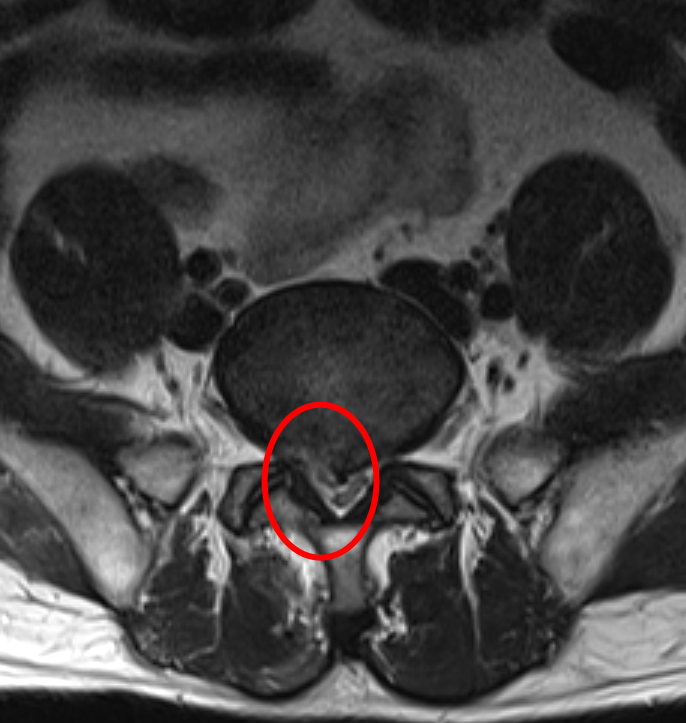

▼術前

從檢查結果看,周先生有很大一塊椎間盤組織脫垂了出來,并壓迫到了神經(jīng),導緻由坐骨神經(jīng)支配的整個右側腰、腿出現比較嚴重的反射痛和麻木感,緻使周先生行走不便,嚴重影響周先生的日常生活、降低了其生活質量。因此脊柱外科建議周先生進(jìn)行經(jīng)椎間孔鏡下髓核摘除術,爲周先生的神經(jīng)根進(jìn)行減壓。